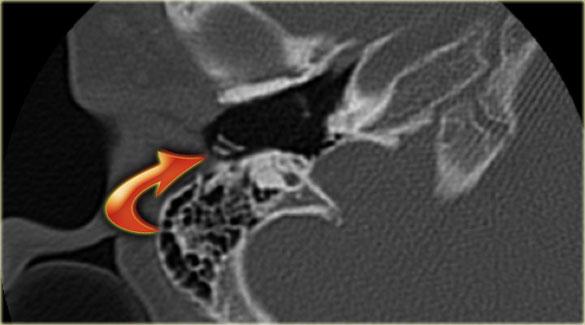

Các hình ảnh này cho thấy một điện cực cấy ghép bị lạc chỗ.

Điện cực ốc tai được đưa vào phía dưới vòng đáy của ốc tai và kết thúc ở vùng hạch gối (geniculate ganglion).